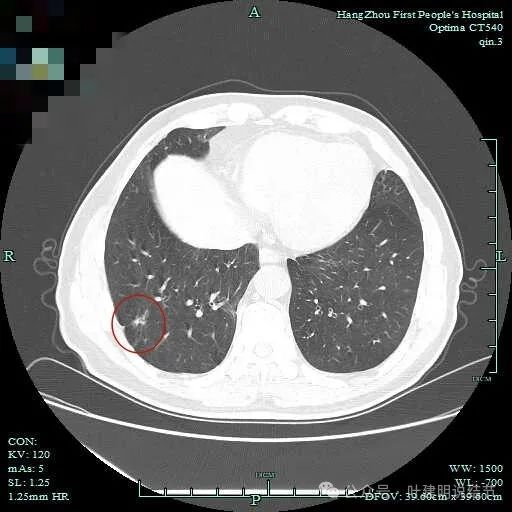

次病灶连续层面观察:

紧贴脊柱处混合密度,趴在脊柱上,这不像结节状。

但有小血管似的,磨玻璃部分界限较清。但此类异常影像在正常人的CT上也挺常见。

密度较高,确实像血管进入。但病灶片状,趴在脊柱上。

此层显得更呈小片状了。

与脊柱间似乎有间隙在,另见微小血管进入这条索状的偏高密度影处。

有细小血管进入,但说不上异常增粗。病灶仍是小片状,条状。

磨玻璃成分密度淡且界欠清,整体就是条索状弯曲的。

上图见细毛刺明显。

病灶实性伴细毛刺,与脊柱间有间隙在。

病仍明显,从上到下,觉得应该是成片的。

表面不平毛刺,实性密度为主。

微小血管有,但无异常增粗。

病灶实性,边缘不光滑。

实性密度,片状,条状。

病灶实性,缺乏膨胀性。

上图呈结节状,表面不平,有少许磨玻璃成分。

结节状,密度高,边缘欠光滑。

与脊柱之间有间隙,表面有细毛刺。

表面不平,似有细支气管截断征。

边缘不平毛糙。

像慢性炎似的。

瘤肺边界欠清。

边缘区淡磨玻璃密度。

1、诊断问题:主病灶是挺典型的恶性表现,而且应该是浸润性腺癌了的,当然不是太致密,仍是早期的可能性大;次病灶纵观应该是片状的,但局部有结节状,结节状的地方,表面不平毛糙,有细毛刺,有血管征,有细支气管截断的样子,此灶感觉不太舒服,但说不是必为恶性。其他结节不确切且风险低,目前不需要管。